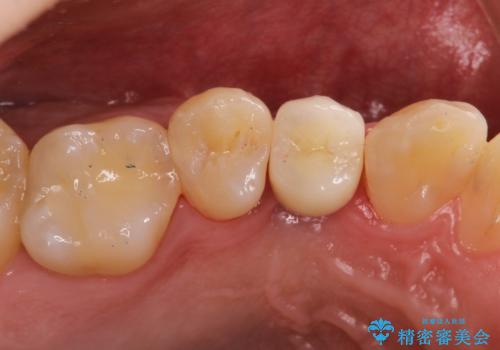

- 歯根破折により抜歯となってしまった患者様です。

インプラントによる咬合回復を行いました。

インプラントによる治療は隣在歯を削らずに咬合回復できるという利点があります。

セラミッククラウンにより自然な見た目で修復できました。